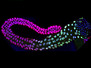

In the intricate microcosm of our bodies, different diseases may interact with each other. For example, researchers are exploring links between serous ovarian cancer (SEOC), the most common form of ovarian tumour, and the herpes simplex virus. Herpes infects over 65% of the world’s population, so is likely to occur in most SEOC patients. It also encodes small molecules, microRNAs, which manipulate gene activity; these are found in the ovaries of SEOC patients at higher levels than in healthy individuals. Each column here shows a section of cancerous tissue, with cell nuclei in blue, the tumour in yellow and surrounding connective tissues in green. In the last two columns, the merged images in the top row reveal the presence of microRNAs (in pink) in the tumour. Specific types of microRNAs are associated with more or less severe cancers, suggesting that further research into their function could help develop potential treatments.